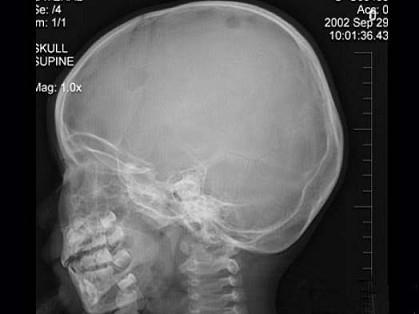

问题 3岁男孩,发热伴头顶部局限性疼痛1周,头颅正侧位示右侧额顶部局限性骨皮质缺损,最可能的诊断是 ( )

选项 A、局限性骨皮质缺损 B、先天性颅骨缺损 C、嗜酸性肉芽肿 D、蛛网膜颗粒压迹

答案 C